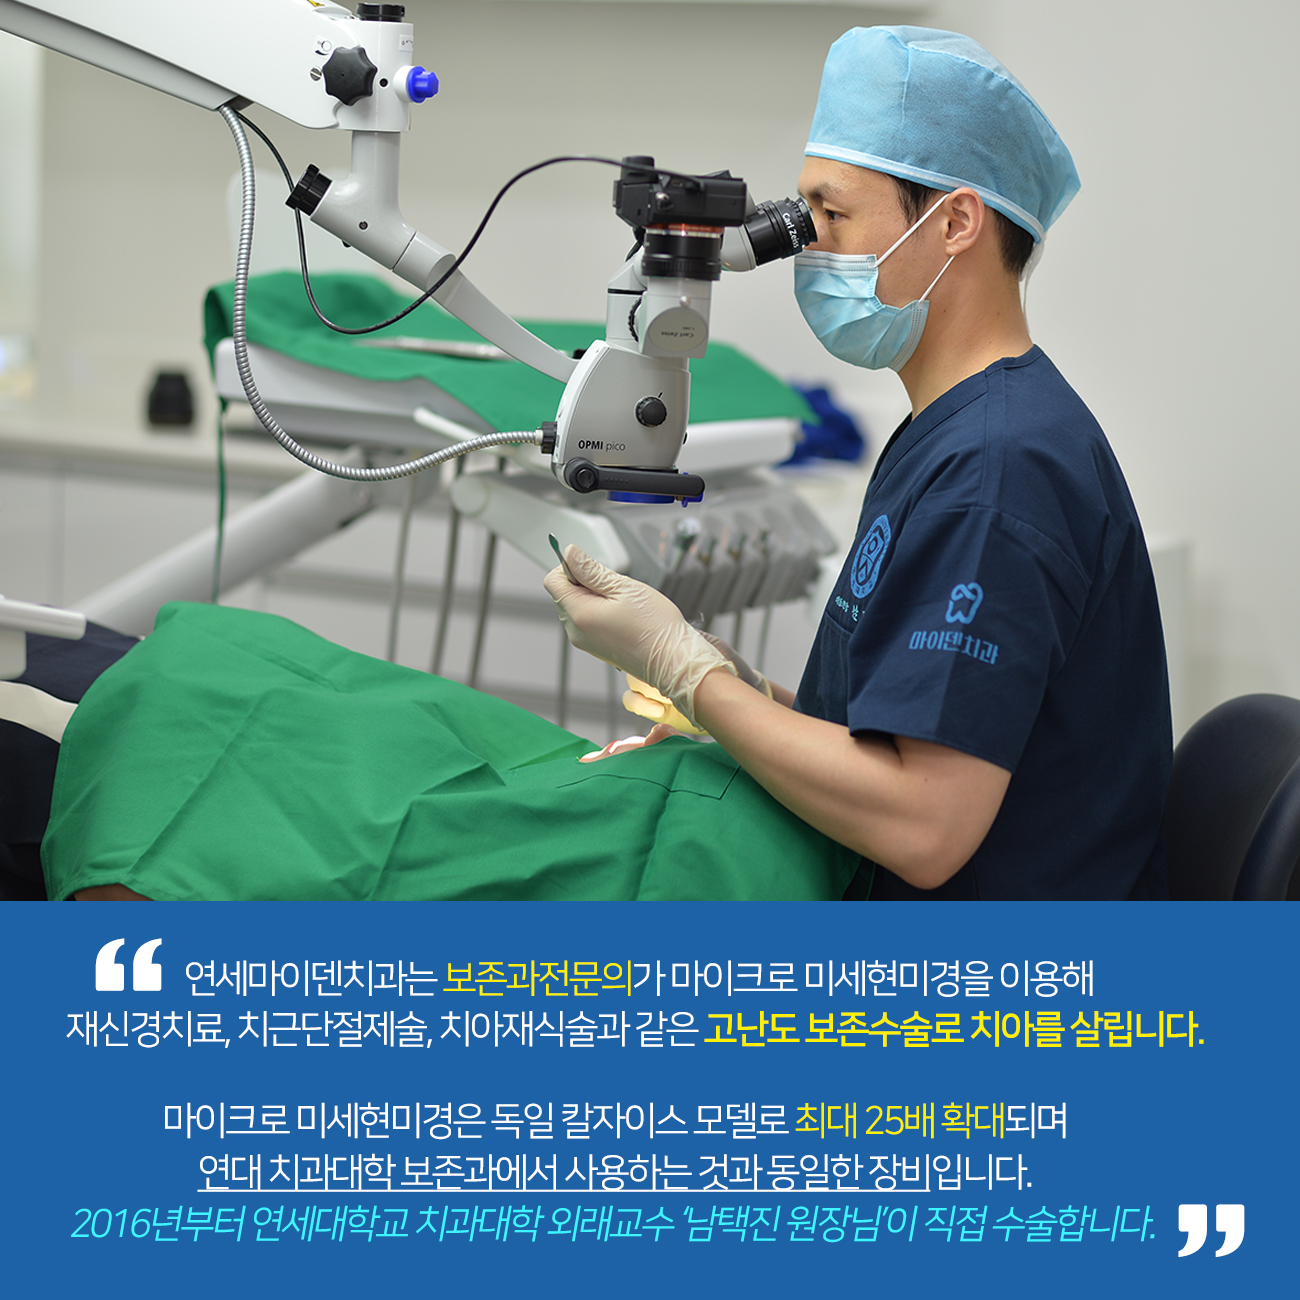

연세마이덴치과 Tel.: 02-6263-2828 홈페이지: www.myden.kr email: myden@myden.kr ● 세브란스본원출신 치과전문의 연세대학교외래교수가 직접 진단하고치료합니다. ● 보건복지부 인정 치과전문의 3인이 세